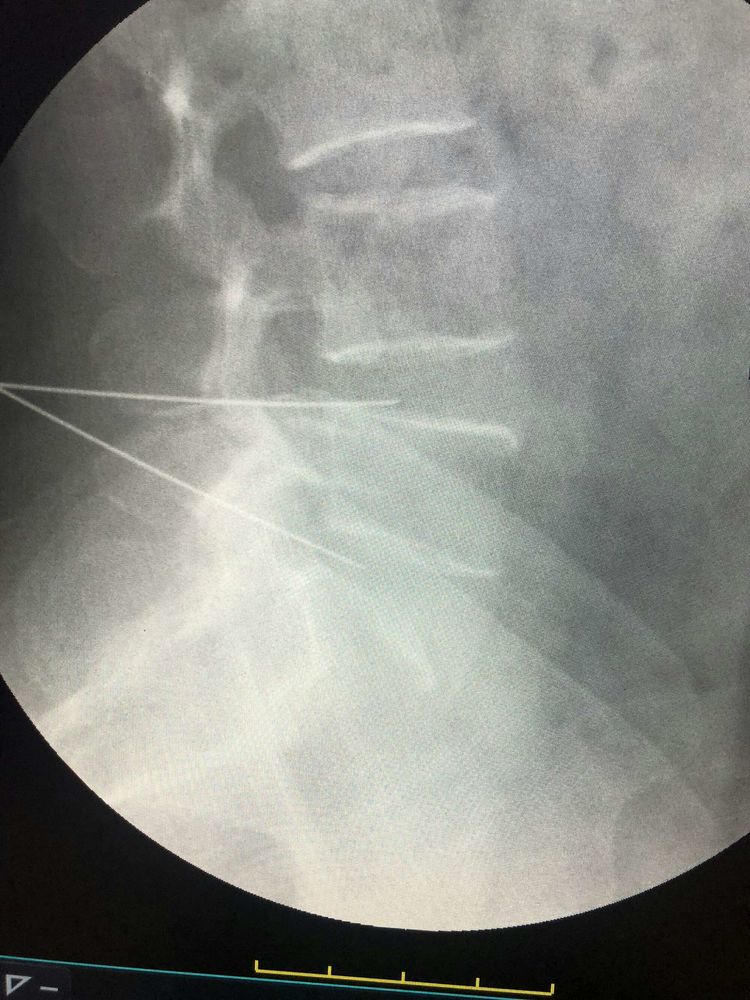

赵清臣主任经皮穿刺骨水泥椎体成形术手术中

①脊柱:老年人骨质疏松症导致的胸腰椎骨折。治疗手段包括经皮穿刺椎体成形术;经皮椎弓根螺钉固定手术;颈、胸、腰椎间盘突出及椎管狭窄的手术切开、摘除、融合;颈、胸、腰椎间盘突出的臭氧治疗;椎间孔镜下颈、胸、腰椎间盘摘除及椎管扩大术;镜下椎间融合并经皮椎体螺钉内固定术;中医药治疗等。